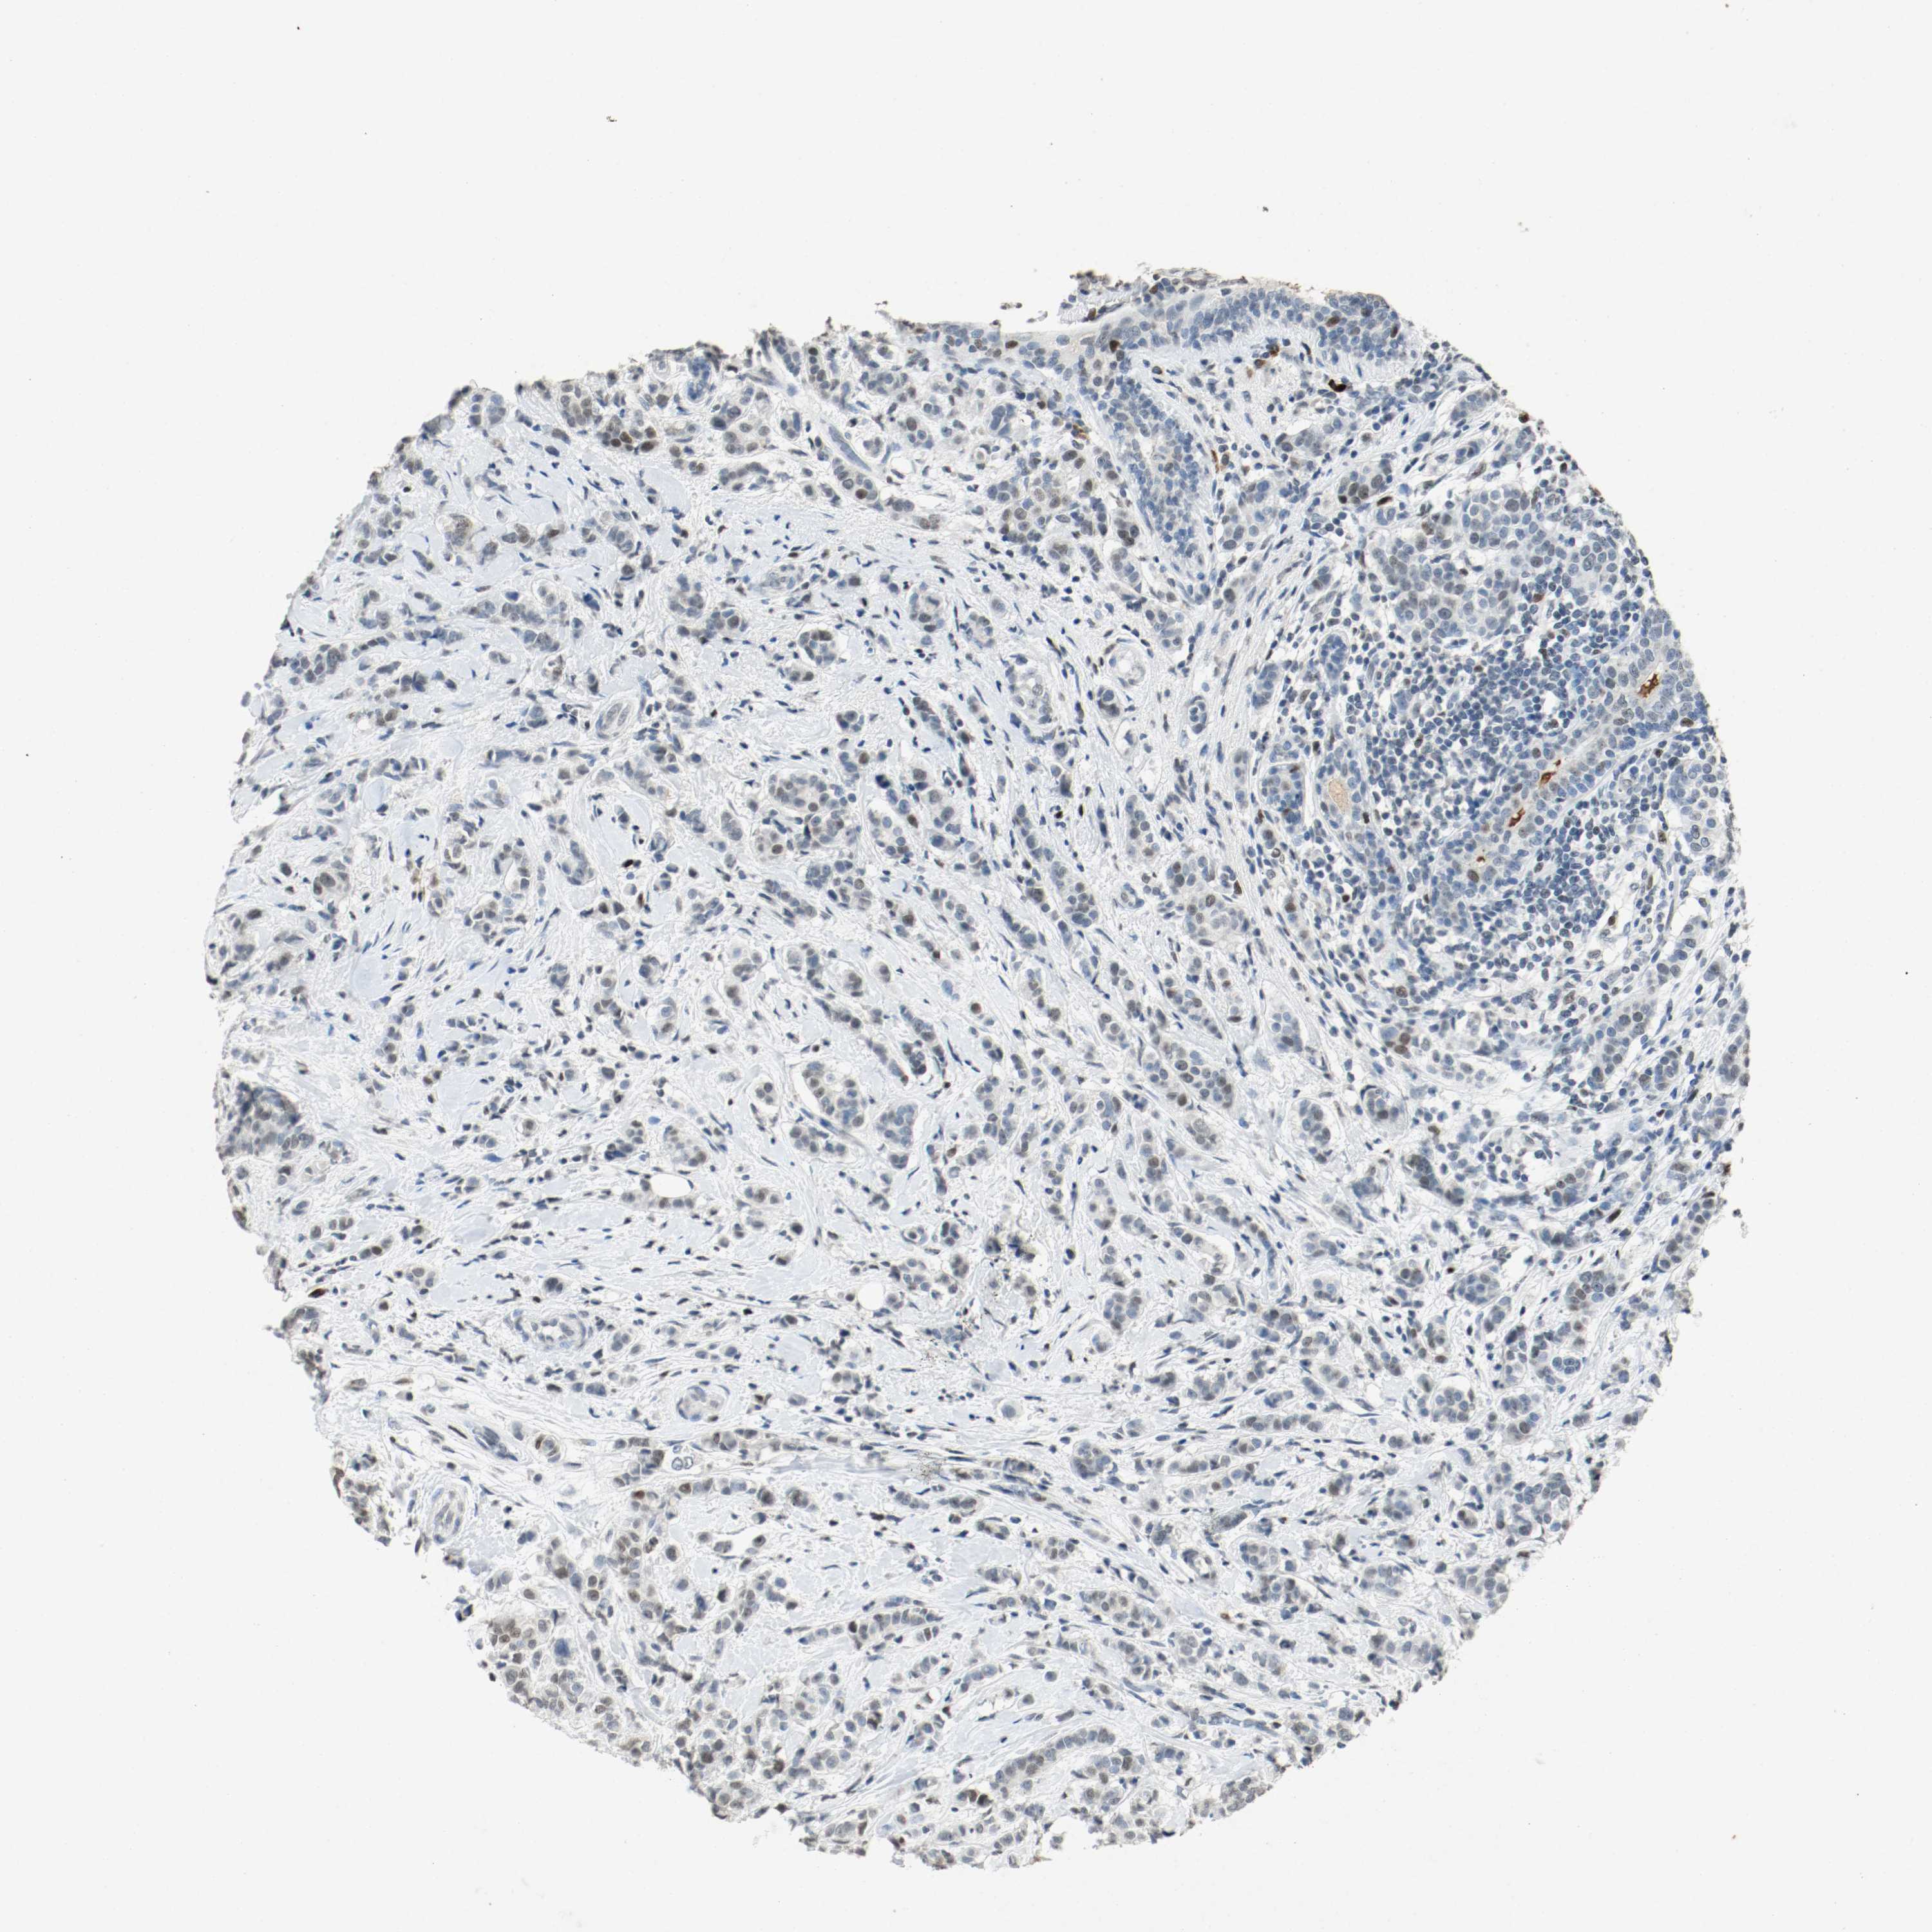

BRCA TCGA BRCA VALIDATION PROTEIN EXPRESSION

Breast cancer

Human cancer